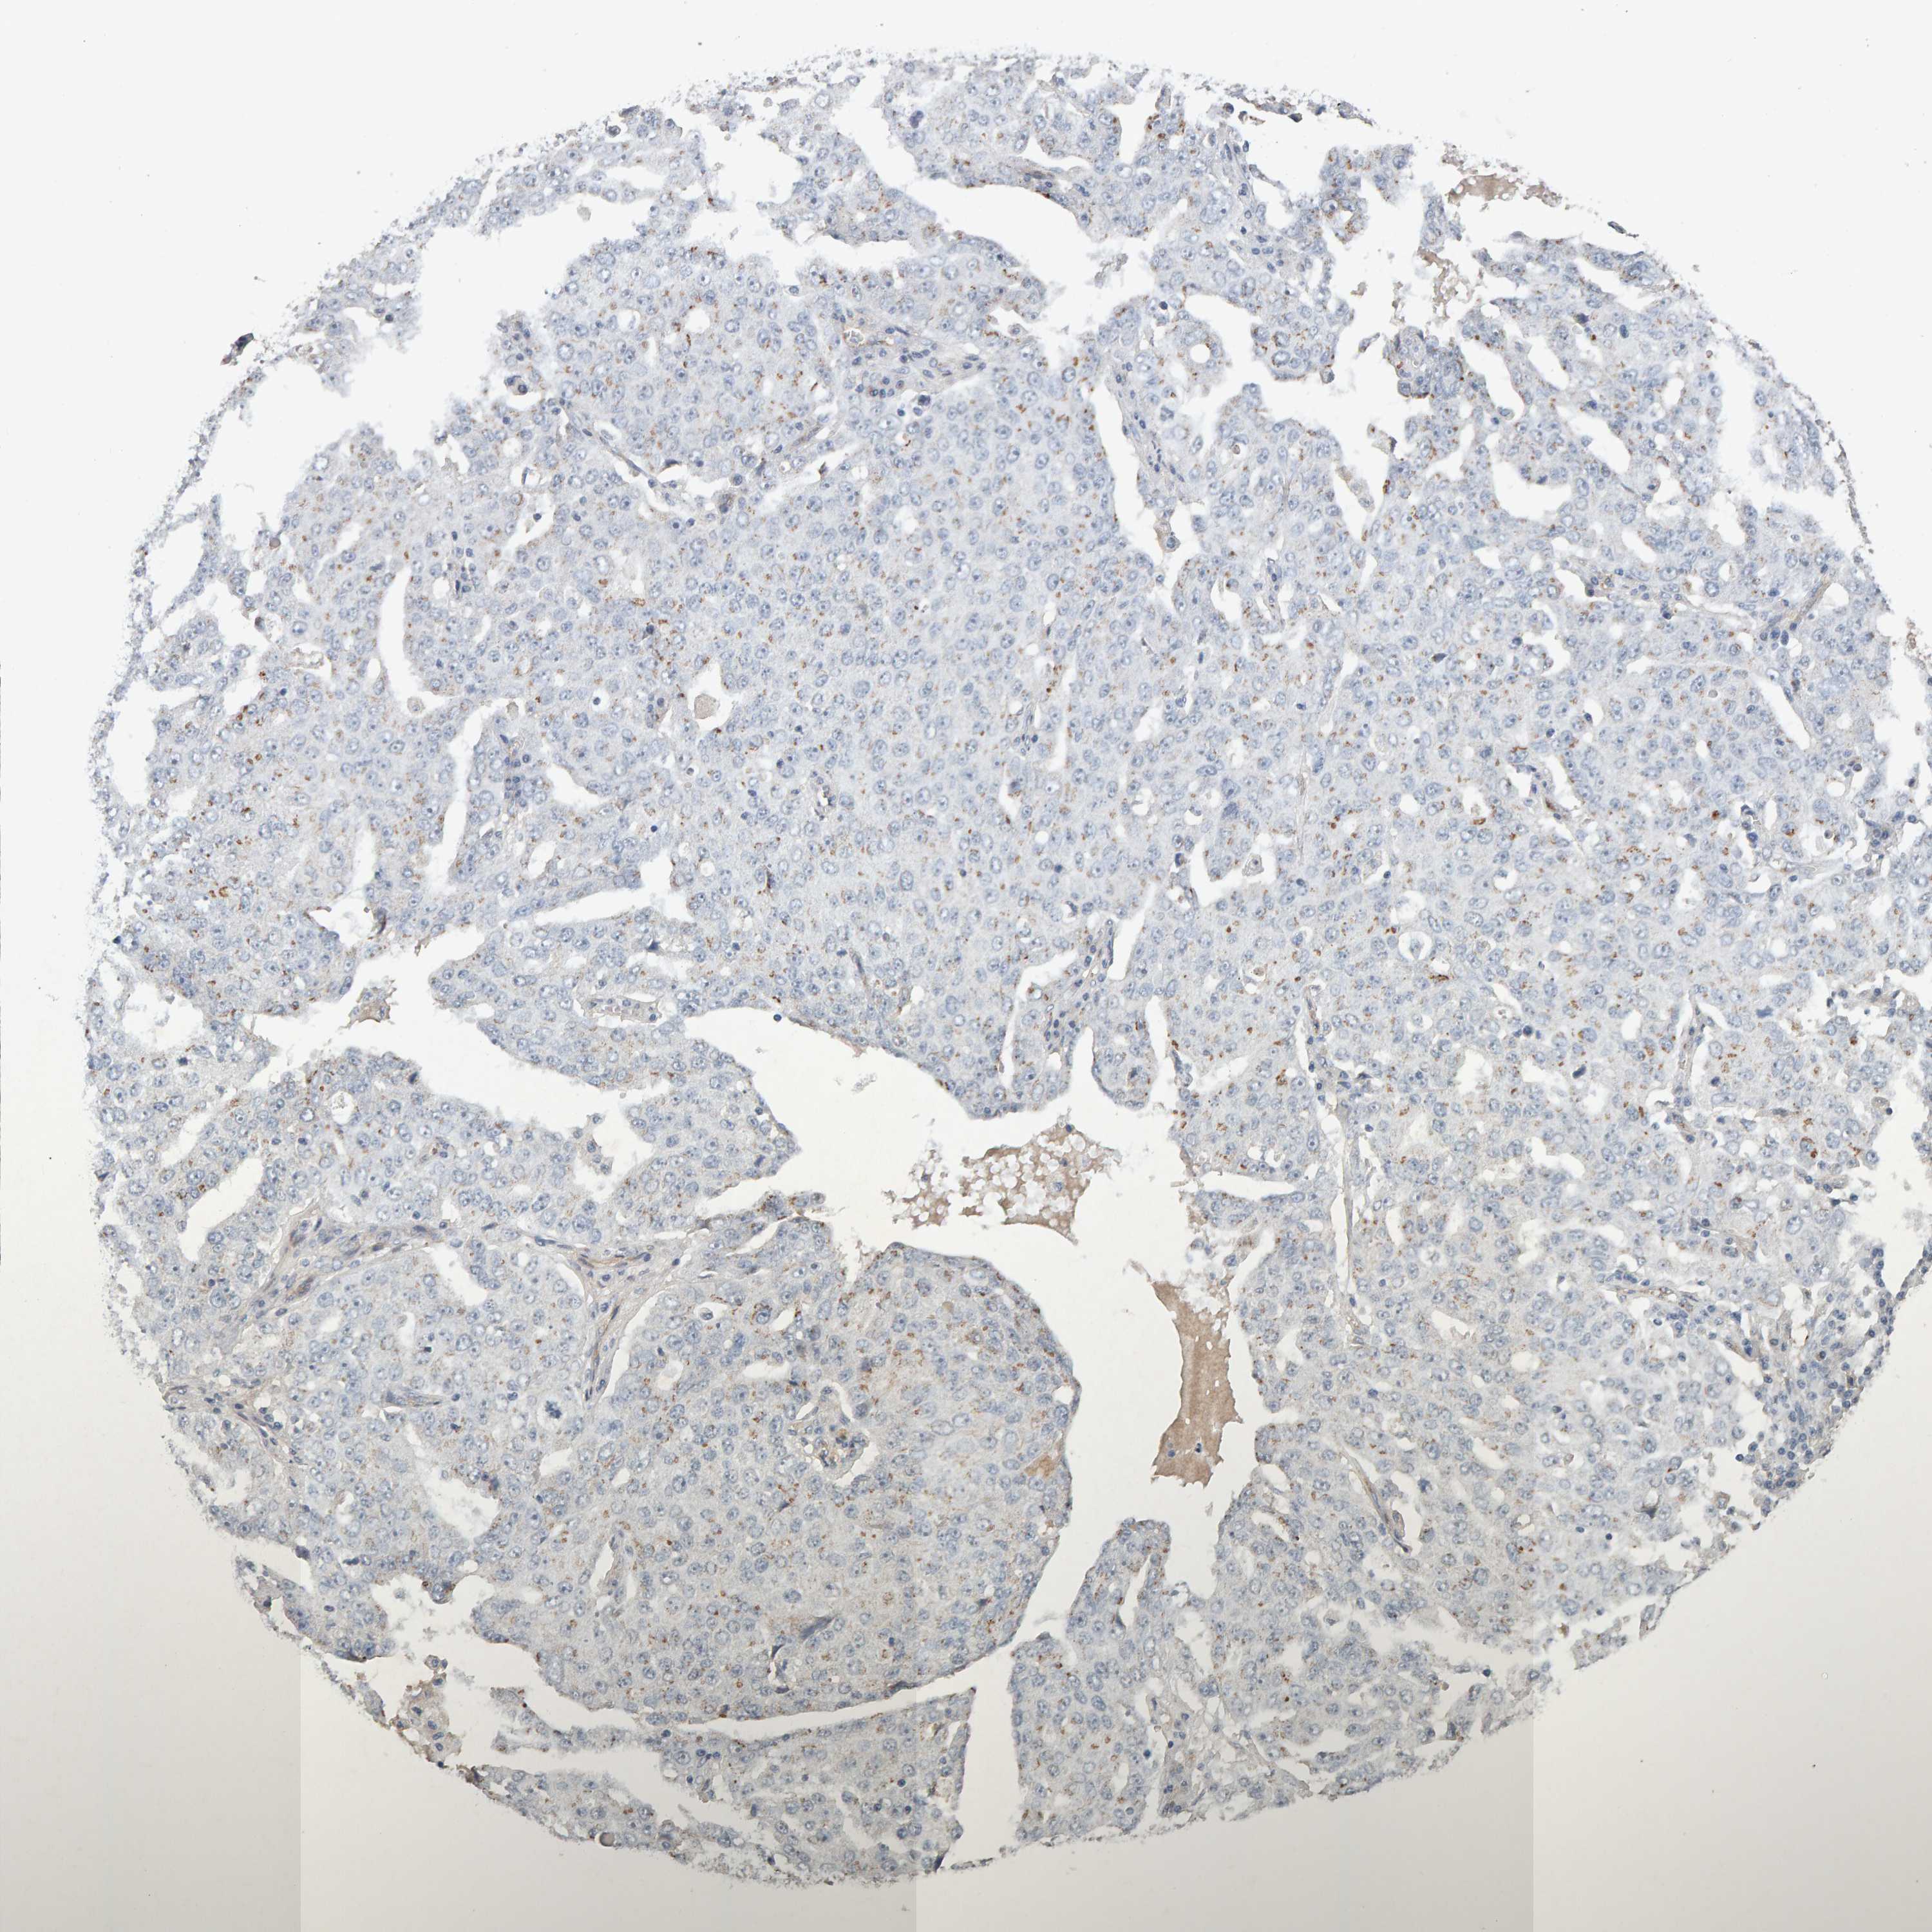

OVARIAN CANCER - Protein expressioni

A mouse-over function shows sample information and annotation data. Click on an image to view it in a full screen mode. Samples can be filtered based on level of antibody staining by selecting one or several of the following categories: high, medium, low and not detected. The assay and annotation is described here.

Note that samples used for immunohistochemistry by the Human Protein Atlas do not correspond to samples in the TCGA dataset.

Antibody stainingi

Antibody staining in the annotated cell types in the current human tissue is reported as not detected, low, medium, or high, based on conventional immunohistochemistry profiling in selected tissues. This score is based on the combination of the staining intensity and fraction of stained cells.

Each image is clickable and will lead to virtual microscopy that enables deeper exploration of all samples and also displays staining intensity scores, fraction scores and subcellular localization as well as patient and tissue information for each sample.

Antibody CAB022442

Antibody CAB022443

Carcinoma, endometroid

Cystadenocarcinoma, serous, NOS

Cystadenocarcinoma, mucinous, NOS

Carcinoma, NOS